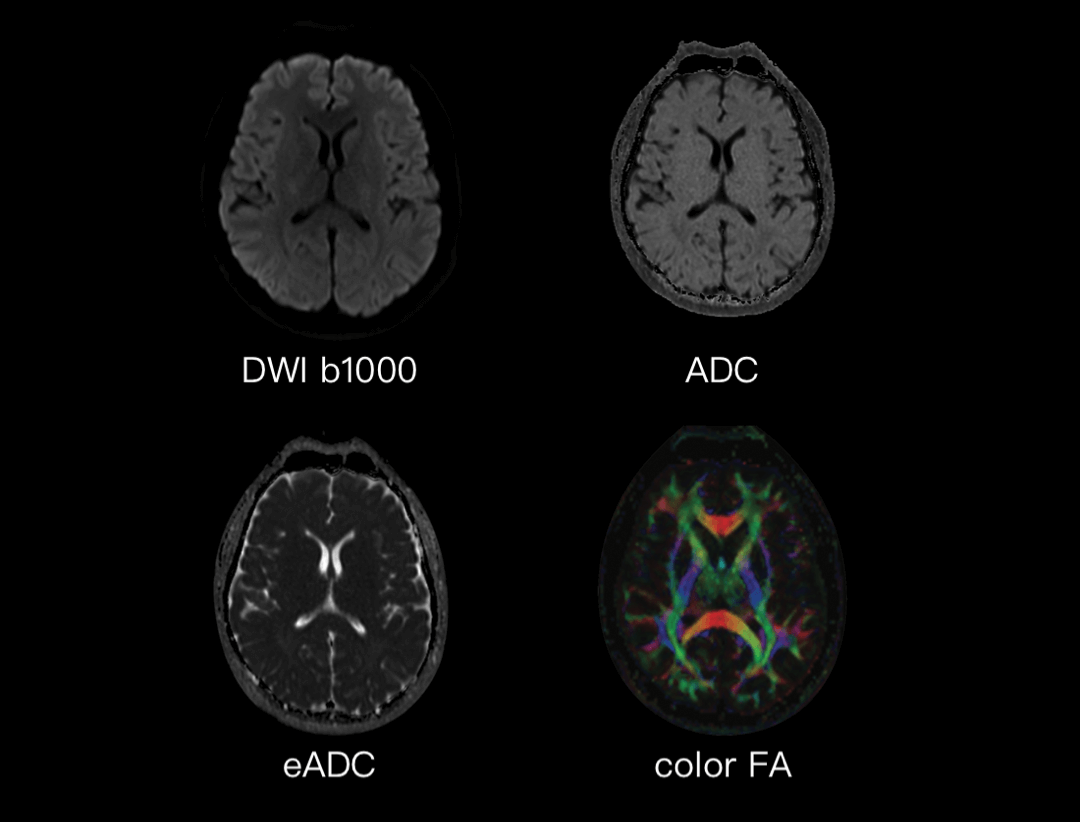

多参数神经成像

提供FA,RA,ADC,Color FA等参数图,能够反映组织内水的运动速度和方向,为疾病诊断,例如脑白质病变提供精准信息。